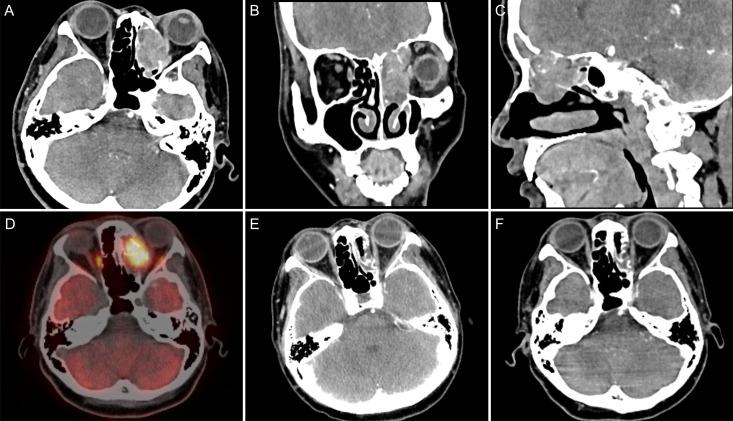

We report the case of a 44-year-old female patient with sinonasal NUT carcinoma who presented with a soft tissue mass in the left frontal sinus, ethmoid sinus, and left nasal cavity on computed tomography; the tumor was poorly demarcated from the left rectus medialis. After discussion with a multidisciplinary team with expertise on head and neck tumors, the patient was considered inoperable, and definitive concurrent chemoradiotherapy (CCRT) was recommended. The patient underwent CCRT followed by three cycles of consolidation chemotherapy with albumin-bound paclitaxel and nedaplatin. Subsequently, the patient underwent 16 cycles of consolidation therapy with the programmed death-1 (PD-1) inhibitor tislelizumab. The immune-related adverse events included grade 2 hypothyroidism. After CCRT, consolidation chemotherapy, and consolidation immunotherapy, the patient achieved a favorable outcome. The patient survived for 31 months, and there were no signs of recurrence or metastasis during follow-up.

我们报告了一例44岁女性鼻窦NUT癌患者,计算机断层扫描显示左侧额窦、筛窦和左侧鼻腔有软组织肿块;肿瘤与左侧内直肌分界不清。在与头颈肿瘤多学科专家团队讨论后,认为该患者无法手术,建议进行确定性同步放化疗(CCRT)。患者接受了CCRT,随后接受了三个周期的白蛋白结合型紫杉醇和奈达铂巩固化疗。随后,患者接受了16个周期的程序性死亡-1(PD-1)抑制剂替雷利珠单抗巩固治疗。免疫相关不良事件包括2级甲状腺功能减退。经过CCRT、巩固化疗和巩固免疫治疗后,患者取得了良好的疗效。患者存活了31个月,随访期间无复发或转移迹象。